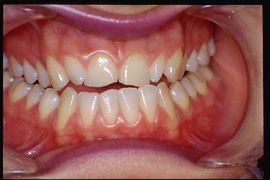

Ad un primo esame clinico occlusale si evince una III classe occlusale funzionale con scivolamento in protrusa nel raggiungimento della massima intercuspidazione. Alla palpazione risultavano dolenti i masseteri, temporali e pterigoidei esterni di ambo i lati. No disturbi di equilibrio e deambulazione, no vertigini no acufeni ma come nostra routine eseguimmo immediatamente gli esami elettrofisiologici trigeminali nell'intento di scongiurare qualsiasi coinvolgimento strutturale del Sistema Nevoso Centrale trigeminale (tNCS). Come già esposto nel capitolo riguardante il paziente 'Balancer' con Meningioma in cui l'esame dello EMG interferenziale eseguito dai colleghi odontoiatrici non dava indicazioni di patologia organica del tNCS nel nostro Centro Diagnostico eseguiamo esclusivamente Potenziali Evocati e la batteria dei riflessi trigmeinali. In questo capitolo, tenendo conto della situazione clinica abbiamo bypassato il contesto puramente odontoiatrico essendo eclatante ma non certo, dopo un primo esame obiettivo, il disturbo malocclusivo (figura 2)

Come possiamo notare partendo direttamente da un contesto neurologico impiegando tecnologie avanzate elettrofisiologico trigeminali abbiamo scongiurato la presenza di destrutturazione del tCNS e contestualmente evidenziato un disturbo occlusale di tipo spaziale. La mandibola con questa metodica che genera un potenziale d'azione sincrono di tutti i muscoli innervati dalle radici trigeminali, a parte condizioni di destrutturazione marcata della ATM, genera una chiusura perfettamente fisiologica che in questo caso viene interrotta dalla presenza di una interferenza dentaria dell'elemento 21 che ci conforta nel proseguire il trattamento neuro gnatologico funzionale.

La finalizzazione del caso clinico diagnosticato definitivamente DTMs ha determinato un ripristino della funzione masticatoria, scomparsa dei sintomi nonché un miglioramento estetico. Le varie fasi della riabilitazioni si possono seguire nella galleria delle immagini della figura 9. In particolare la posizione Centrica Neuro Evocata Funzionale non solo è centrata essendosi spostata leggermente a destra ma anche retrusa. E' interessante fare una comparazione conn la figura 5a per rendersi conto delle differenze spaziali. L'elemento 22, infatti, non è più in crossbite ma in una posizione di testa a testa mentre il 23 ha un contatto centrica molto più incisale rispetto alla situazione clinica precedente, così pure da notare lo spazio occlusale nell'area mediale del 24 che si è venuto a generare con la attuale posizione spaziale mandibolare determinata con la Centrica Neuro Evocata Funzionale. Questo nuovo assetto occlusale è stato possibile solo perchè la posizione centrica stabile e principalmente congelata nel settore dei molari. I molari attraverso l'equilibrio neuromotorio esposto precedentemente sulla cuspide centrica stabilizza l'occlusione e genera un bilanciamento bilaterale nei movimenti mandibolari come sarà a breve descritto.